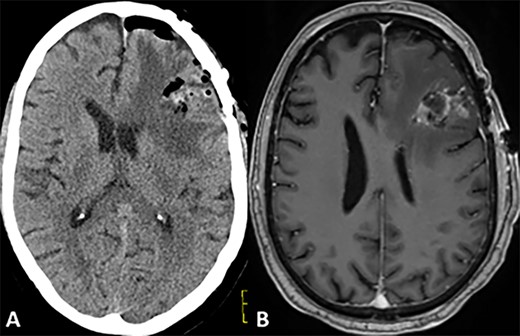

CASE

CT and MRI scans of the head indicating a large hemorrhagic enhancing lesion in the left frontal lobe with surrounding edema causing a rightward midline shift.